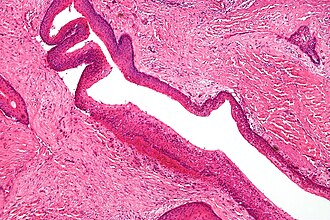

Template:Px Keratocystic odontogenic tumour. H&E stain. | |

| LM | stratified epithelium with "ribbon-like appearance" with palisaded basal cell layer, parakeratosis, artefactual separation of epithelium from the basement membrane |

- Stratified epithelium (resembling squamous epithelium) with:

- "Ribbon-like appearance" - important.

- Typically 8-10 cell layers thick - with relatively uniform thickness.

- Lacks rete ridges.

- Palisaded basal cell layer.

- Parakeratosis (keratinized cells with nuclei) - key feature.

- Artefactual separation of epithelium from the basement membrane.